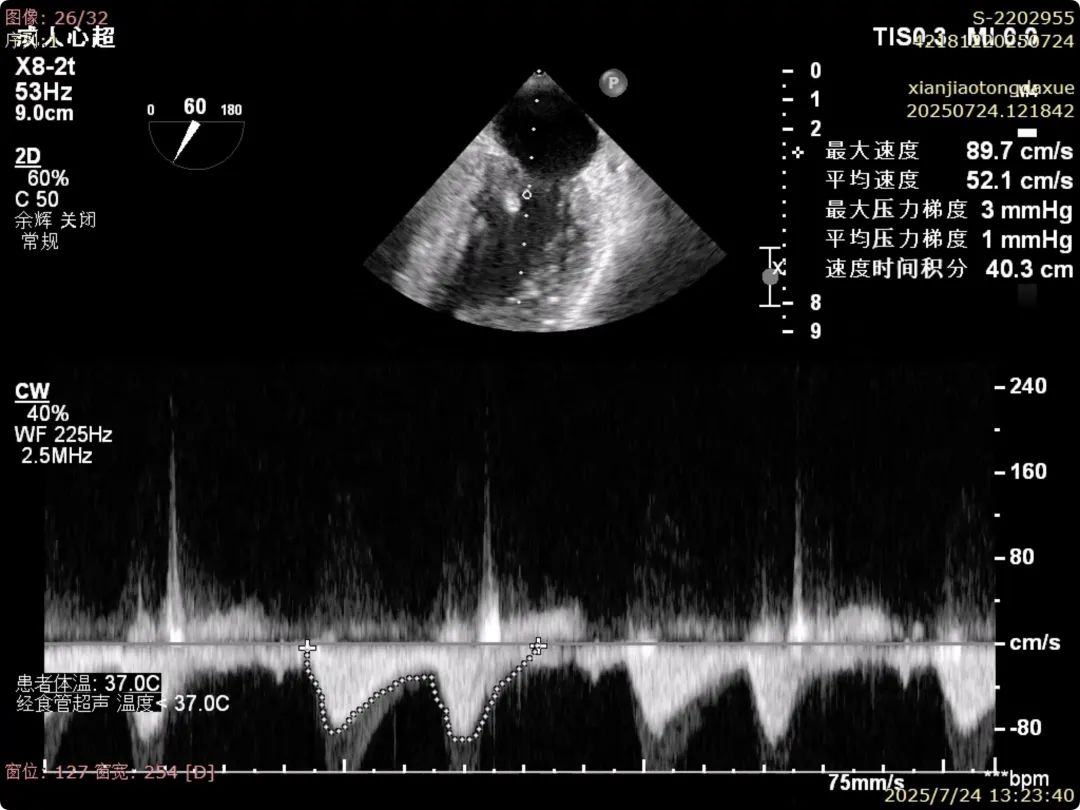

术后夹合数据确认,达到预期效果